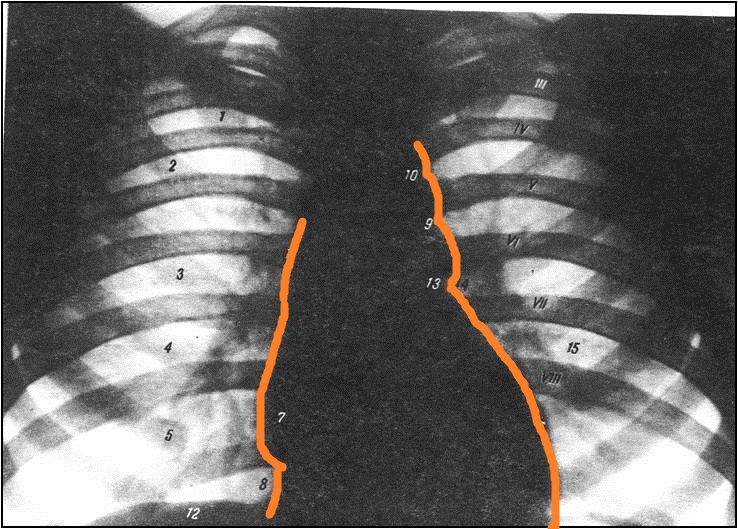

V2: Тема 4.3 Печень, поджелудочная железа, селезенка. Топография брюшины. Рентгенанатомия органов брюшной полости.

S: Анатомическое образование, обозначенное цифрой 15 - valva ### (лат.яз).

S: Анатомическое образование, обозначенное цифрой 14 - ### (лат.яз).

S: Цифрой 16 обозначен - valva### (лат.яз).

S: Цифрой 17 обозначен - valva### (лат.яз).

S: Цифрой 13 обозначены - musculi### (лат.яз).